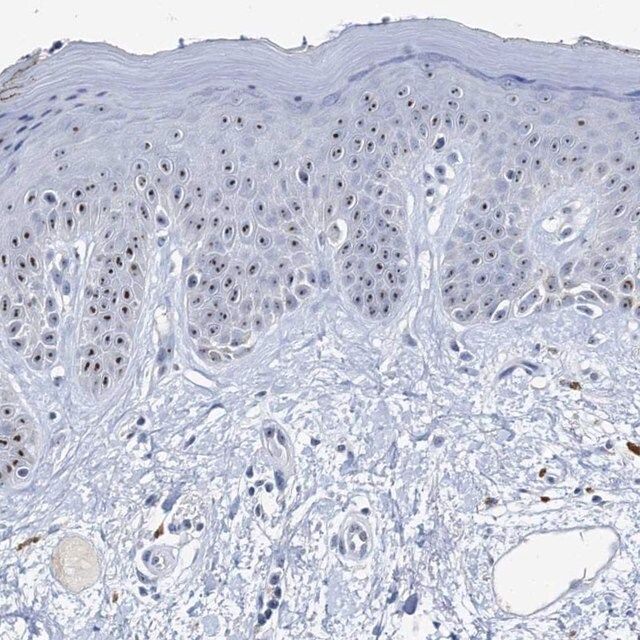

| General description【一般描述】 | Nucleolar protein 2 (NOP2) is encoded by the gene mapped to human chromosome 12p. NOP2 is a 120kDa protein. It is expressed in adult human brain and is specifically localized on a novel nucleolar microfibrillar structure. |

| Biochem/physiol Actions【生化/生理作用】 | Nucleolar protein 2 (NOP2) might be involved in the ribosomal synthesis and the cell cycle regulation. NOP2 is used as a marker in several cancers, including breast and lung carcinomas. The encoded protein interacts with telomerase and activates cyclin D1 gene transcription and thus, play a key role in regulation of cell proliferation. |

| technique(s) | immunoblotting: 0.04-0.4 μg/mL immunofluorescence: 0.25-2 μg/mL immunohistochemistry: 1:500-1:1000 |